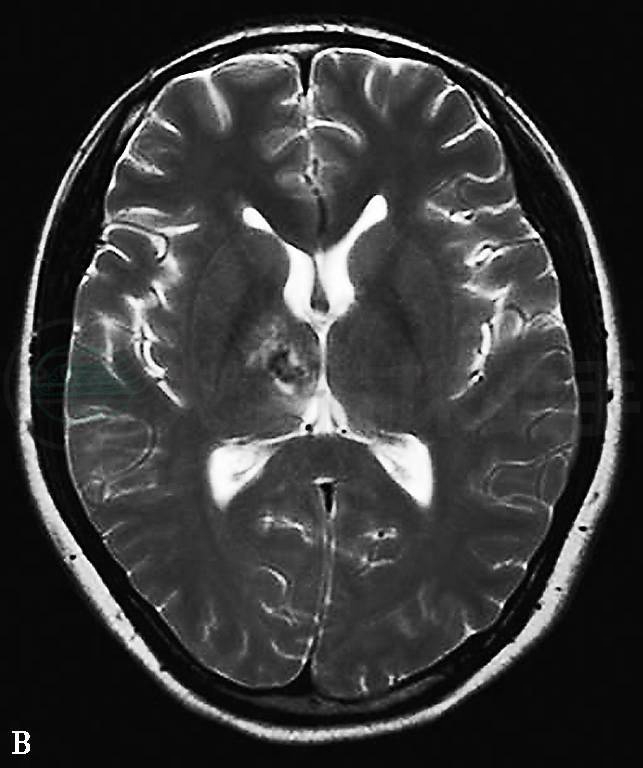

2011年10月24日神经系统查体未见异常,当天复查腰穿:CSF无色透明,压力150mmH2O,WBC 7/mm3,RBC 15/mm3,生化正常,涂片细菌、真菌(-)。停用利奈唑胺。复查血常规恢复正常。10月25日复查头颅平扫及增强MRI:病灶缩小至大小约1.0cm×0.5cm,水肿及占位效应明显减轻,中线结构居中,脑室系统恢复正常(图3)。

图3 2011年10月25日头颅MRI:病灶明显缩小,水肿及占位效应明显减轻。病变在(A)T1WI上可见环形稍高信号,(B)T2WI上中心见低信号影,提示少量出血伴周围胶质增生。(C)增强扫描病灶仍有少许斑片状强化。中线结构居中,脑室系统恢复正常